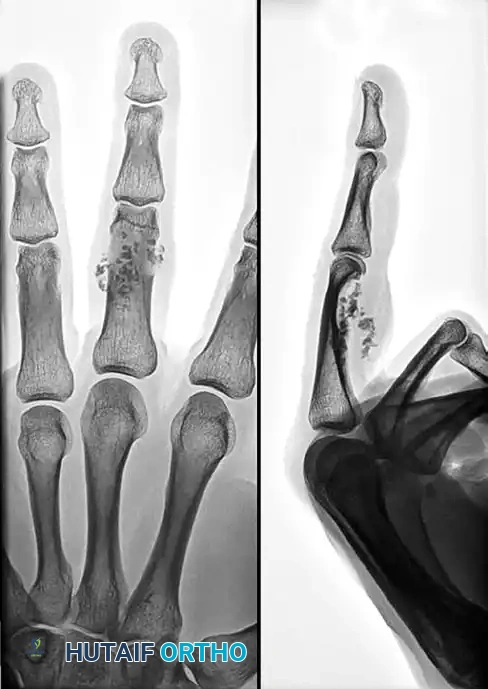

FIGURE 77-20 A: Anteroposterior and lateral radiographs of a 32-year-old man with insidious swelling of the left middle finger. Note the multiple spotty calcifications clustered around the proximal interphalangeal (PIP) joint.